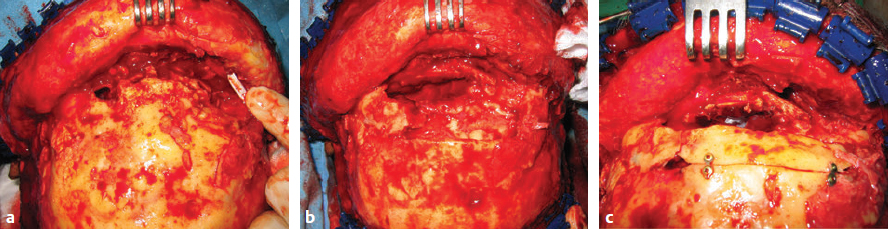

CHAPTER Traumatic injuries to the craniofacial complex can be devastating. Long-term sequelae lead to disfigurement and dysfunction if not managed appropriately. Trauma to the face can involve soft tissue, bone, salivary glands, or sensory organs. Initial management of facial trauma follows Advanced Trauma and Life Support guidelines. Once stabilized, facial injuries are treated. To optimize outcome, a systematic approach should be undertaken: 1. Accurate diagnosis by physical examination and supporting radiographic studies 2. Formulation of optimal surgical timing as well as methodology of surgical repair 3. Proper execution of treatment plan, including: • Adequate surgical exposure while following basic aesthetic principles • Anatomic reduction • Stable fixation • Optimal soft tissue management and resuspension 4. Early mobilization and proper rehabilitation Despite best efforts, treatment results of facial trauma may be suboptimal. Reduction may collapse over time because of cicatricial or muscular forces. Bony malunion or nonunion may occur. There may be poor scar formation or neurologic injury secondary to operative treatment. Unfavorable outcomes should be approached in a similar fashion to the initial injury. A methodical approach that begins with a physical examination supported by radiologic studies followed by goal-directed surgery leads to success. H.K. Kawamoto (personal communication, 2016) reiterates, “You have to know what the problem is before you can fix it.” This chapter discusses the treatment for unfavorable results of upper and midface fractures. Although rare in the facial area, infection is the first complication surgeons must watch for postoperatively. The time course may be in the initial days after the operation, but infection may not present until weeks or months later, in the form of hardware infection and exposure. If signs of infection are noted in the acute phase of healing, then simply releasing sutures or staples and gently reopening portions of the wound can be beneficial. This allows egress of infected material and exposes the wound to oxygen, inhibiting anaerobic bacterial growth. Many practitioners choose to treat perioperatively with a 5- to 7-day course of oral antibiotics that covers oral flora. For an infection that is more physiologically severe or when clinical evidence of an infection progressing beyond a localized wound is present, hospital admission is indicated. Treatment includes volume resuscitation, parenteral antibiotics, and débridement of infected tissues. Hardware infections present either in the early or late stage as exposure or purulence around plates and screws. Hardware exposure can often be treated conservatively until bony healing is complete. If bony union is not achieved, the hardware pockets are irrigated of frank purulence and débrided conservatively. The wounds can then be reclosed over a drain and a course of antibiotics given. After bony union is achieved, the hardware can then be removed. Osteomyelitis is uncommon in facial bones but can occur after excessive periosteal stripping and contamination of a fracture. Osteomyelitis presents with localized (rubor, calor, dolor) or systemic (fever, myalgias) infection. Osteomyelitis is diagnosed by a combination of bone biopsy and specific radiographic findings.1,2 Management of osteomyelitis includes surgical débridement of affected bone, removal of all internal hardware, maintaining bone orientation, and 6 weeks of intravenous antibiotics.3,4 The remaining bone segments’ orientation may be maintained by external fixation devices or replacement of plates. If the surgeon chooses to replace the internal plates, then load-bearing reconstruction plates are preferred with locking screws placed away from the site of infection in well-vascularized, healthy bone. Summary Box Unfavorable Results and Complications in the Treatment of Facial Trauma • General • Frontal sinus fractures • Naso-orbitoethmoid fractures • Orbital fractures • Zygomaticomaxillary complex fractures • Nasal bone fractures • Le Fort fractures • Panfacial fractures Scar formation from traumatic soft tissue injuries affects the result as much as bony reduction. Often, cicatricial formation of the face leads to aesthetic and functional impediments. Lacerations with crushed edges, avulsed hypoperfused superficial tissue, increased bacterial burden and local inflammation, and tight wound closure all combine to increase scar formation. To optimize cutaneous wound healing, patients should be advised to avoid sun exposure and perform scar massage or topical treatments. Massage mechanically softens the scar tissue and counteracts cicatricial thickening and contraction. Silicone gel or sheets improve scar contour and thickness.5,6 These interventions can be started after the removal of suture, provided the wound is healing well, typically after 10 to 14 days. Hypertrophic scarring appears at 3 to 4 weeks and can potentially be inhibited by serial intralesional steroid injection.7,8 This intervention will act locally to inhibit scar tissue formation. Immunomodulators such as 5-fluorouracil have also been shown in some studies to be effective.8–10 Laser and phototherapy may decrease the prominent redness of scars.11,12 If an unaesthetic scar persists beyond 6 to 8 weeks despite optimal scar therapy, scar revision and excision may be performed. This may be performed as a simple excision or other forms of local tissue rearrangement. The timing for revisions generally allows 3 to 6 months of healing to permit full resolution of tissue inflammation. As is the case with any elective procedure, it is important to medically optimize the patient for wound healing. The patient should be nutritionally optimized, tobacco free, and under adequate glycemic control. Full scar excision removes chronic inflammation and allows closure with noninflamed tissue. The wound should be designed in a way to hide it within the resting tension lines of the face, as well as to allow local tissue recruitment and tension-free closure. Abnormal fracture healing results in delayed union, nonunion, or malunion. Delayed union is slow or delayed bone healing. This occurs in cases with prolonged tissue inflammation, infection, or insufficient bone stabilization. Insufficient stabilization may be caused by screw loosening, fractures of the bone adjacent to hardware, or plate fracture. Delayed union becomes nonunion when bone fails to ossify after adequate healing time.13 A nonossified fibrous bridge often forms between bone ends and is mechanically insufficient to support the fractured segments, resulting in structural collapse against adjacent muscular or cicatricial forces. Nonunion is more likely to occur in the mandible than in the maxilla, where the forces supported are greater. Malunion is nonanatomic postreduction alignment of proximal and distal bone.14 Malunion follows poor reduction as well as hardware loosening and failure. Malunion presents with clinical findings of a step deformity at fracture segments, malocclusion, or an asymmetrical facial contour. The evaluation of malunion or delayed nonunion starts with a physical examination. It is appreciated by facial bone mobility, step-off, and asymmetry. The physical examination is followed by radiographic imaging. Computed tomography (CT) provides a thorough evaluation for bony gaps and nonviable bone. If vascularized bone flaps are necessary, CT angiography can confirm donor vascular anatomy of the flap. In these cases, the patient should be fully evaluated for physiologic tolerance for prolonged surgery. The treatment for bony nonunion involves removing the previously placed hardware and excising the fibrous bridge. Bone, as free or vascularized graft, is then used to bridge the segment, and the entire construct is supported by hardware. The length of the bone gap is important because it determines the treatment. Nonvascularized or allogenic cadaveric bone grafts adequately reconstruct defects up to 6 cm, whereas vascularized bone grafts, from the fibula or iliac crest, are ideal for defects larger than 6 cm.15 For a defect smaller than 6 cm in a nonirradiated patient, treatment options include cadaveric or nonvascularized autogenous bone graft. Adding a substance such as bone morphogenetic protein (BMP) to this site may improve osteoinductive potential, through direct stimulation of bone growth and induction of bone stem cells. These nonvascularized corticocancellous grafts are secured to the bone plate within this continuity defect. Bony defects larger than 6 cm require reconstruction with vascularized bone flaps. With these large bone gaps, vascularized bone provides osteogenic potential for healing and prevents the resorption seen in conventional bone grafts. Possible donor sites include the fibula, iliac crest, scapula, and radius, each with their own set of advantages and disadvantages. Flaps may be transferred as bone and soft tissue composite free tissue to correct soft tissue deficits. The frontal sinus begins to develop at age 6 years. In adults, the sinus is completely formed as air-filled spaces in the forehead on either side of the midline. With an average total volume of 14 mL, the frontal sinuses are composed of an anterior and posterior wall and can exist as two separate spaces separated by a bony midline septum or a large communicating single cavity.16 Mucosa lines the bony cavity and produces secretions that drain through nasofrontal ducts traversing the inferomedial sinus floor and to the nasal middle meatus. The anterior wall forms brow and forehead contours, whereas the posterior wall forms the limit of the anterior cranial fossa. Fractures of the frontal sinuses have many patterns and can include one or both sinuses; involve the anterior wall, posterior wall, or both walls; and may or may not extend to or cause obstruction of the frontal duct system. Initial treatment involves three considerations that determine the outcome. The anterior wall supports the aesthetic contours of the brow and forehead. The posterior wall supports the anterior cranial fossa and dura. Fractures injure the dura and form a communication between the brain and nasal cavity. The nasofrontal duct drains the sinus, and obstruction can lead to trapping of secretions and infection. Management of these fractures focus on restoring integrity of the anterior walls but also on the creation of what has been conceptually referred to as a safe sinus.17,18 This concept refers to preventing mucous trapping by removing mucosal elements of the sinus when the nasofrontal ducts are compromised or intracerebral infection is of concern. The initial treatment of frontal sinus fractures starts with prophylactic antibiotics. Antibiotic choice should cover gram-negative, gram-positive, and anaerobic bacteria, such as clindamycin. Anterior table fractures are reduced and plated into anatomic position. Injury to the nasofrontal duct is treated by sinus obliteration, removal of all mucosal elements, and closure of the nasofrontal duct. Displaced fracture of the posterior wall is treated by (1) cranialization, (2) removal of the posterior wall, (3) removal of all mucosal elements, and (4) repair of dural injuries. Reconstructive failure of these four elements may create undesirable results. Contour irregularity of the forehead and glabella result from loss of soft tissue, bone fragment resorption, or inaccurate realignment of the bones. If this occurs, it may be noticeable and become a stigmata of previous injury, sometimes causing patient distress. Evaluation starts with physical examination followed by CT. Scans can determine whether the aesthetic abnormality is related to soft tissue atrophy or underlying bony irregularity. Bony irregularity in the form of overlapping step deformity or irregular thickness can be burred or filed down. Options to improve soft tissue contour defects include soft tissue grafts like fascia, dermis, or fat. For large or bony defects, bone grafts as well as alloplastic materials such as prefabricated polyethylethylene or porous polyethylene may be used. Each of the aforementioned materials has its proponents, depending on the size and type of contour. Autogenous options are superior because of a decreased potential for infection or granulomatous reactions. Overcorrection is indicated to account for the expected fat and bone graft resorption over the first year and beyond (Fig. 48.1). Fig. 48.1 (a,b) A young patient presented after posttraumatic frontal sinus and bone repair with significant frontal and cranial bone loss. (c) Split calvarial bone was used to reconstruct the frontal bone, glabella, and forehead. (These images are provided courtesy of J.I. Garri.) Meningeal tears and injury can result in persistent cerebrospinal fluid (CSF) leak and secondary CSF space infection. This can either result from poor healing and sealing of the dural closure or unidentified dural tears. Evaluation for a chronic CSF leak is a clinical diagnosis but can be verified by beta-transferrin levels of the fluid. The clinical presentation is persistent clear nasal drainage. CT may be useful to identify the location of the dural defect. Dural defects are repaired by direct suture or using dural patches of free fascial graft or alloplastic collagen sheets.19,20 A preferred method is the use of vascularized pericranium or temporalis to cover suture lines (Fig. 48.2). When there is significant dead space and continued CSF leak, pericranium and temporalis flaps may be insufficient. These situations may be best dealt with using free tissue transfer, which can fill dead space, improve vascularity to the region, and stimulate sealing of the dura.21 Mucoceles of the frontal sinus result from sequestered secretions caused by partial or complete nasofrontal duct obstruction. They occur when there is an unrecognized nasofrontal duct obstruction or because of retained sinus mucosa after obliteration or cranialization and may occur years after the initial injury.22,23 Infected mucoceles are called mucopyoceles. Mucoceles expand from continued mucous secretion and compress and distort surrounding structures. Diagnosis is clinical, based on a history of frontal sinus fracture, fevers, visual symptoms, and headaches. CT defines the patient’s anatomy and structural distortion caused by the mucocele (Fig. 48.3). Early treatment of mucoceles involves ample drainage, which can be performed endoscopically if identified before significant anatomic distortion. If endoscopic drainage fails or is not technically feasible, a craniotomy is required to remove all retained sinus mucosa. Through a coronal incision, a craniotomy allows access to the mucocele. The brain is separated from the mucocele, and any inflammatory tissues are removed. The posterior table segments are removed and any remaining sinus surfaces are burred to remove all mucosal rests. Distorted facial and cranial structures are reconstructed with autologous bone graft (Fig. 48.4). The dead space is then obliterated by a pericranial or temporalis flap.23 If these are too scarred for use or have been used already, or the dead space is large, the surgeon must consider alternate options such as free tissue to close off those spaces. Fig. 48.2 A collagen alloplastic patch is used to seal the dura. (This image is provided courtesy of J.I. Garri.) Fig. 48.3 After a frontal sinus fracture, this patient presented with a left-sided mucopyocele that destroyed the orbital roof and rim. (This image is provided courtesy of J.I. Garri.) Fig. 48.4 (a) After a frontal sinus fracture with mucopyocele formation, this patient’s anterior table had irregularity and openings into the sinus. (b) Resection of necrotic bone exposed the sinus and allowed débridement of the mucopyocele and separation from the brain. (c) Reconstruction is with split calvarial bone graft. (These images are provided courtesy of J.I. Garri.) The naso-orbitoethmoid (NOE) region is a complex focus of bony articulations involving multiple facial buttresses. Here the nasal bones and cartilages, maxillary frontal processes, lacrimal bones, orbital plate, ethmoid air cells, cribriform plate, and frontal bone adjoin. NOE fractures affect the shape and position of the nasal pyramid, root of nose, and medial canthus. Accurate reduction prevents contour and symmetry irregularity of the nasal sidewall. The grade of injury determines the surgical maneuvers necessary to correct the medial canthal deformities. This includes reduction or fixation of fractured segments and transnasal wiring. Telecanthus is an increased distance between the medial canthi.24 It is a soft tissue relationship and differs from hypertelorism, which is increased interpupillary distance.25 The normal intercanthal distance equals the length of the patient’s palpebral fissure, approximately 31 to 33 mm.26 This is a gender-specific and ethnically variable measurement. Malpositioned medial canthi is a challenging problem to correct. Poor medial canthal position and appearance can be caused by soft tissue secondary healing and bone malposition. The evaluation should include a keen physical examination correlated with CT to better define the bone and soft tissue relationship. Scarring and fibrosis of the soft tissue around the medial canthal tendon distorts its position, leading to degrees of telecanthus. Alternatively, the previous medial canthal wiring may erode the bone and allow the canthus to slip laterally. This situation is most easily addressed with tissue rearrangement using small, local flaps. Horizontal discrepancies can be corrected with V-Y advancement, whereas vertical discrepancies are addressed with z-plasty–style transposition flaps. These flaps should be full-thickness tissue down to bone. The flap controlling the canthal angle is then reanchored to bone by a transnasal suture or wire to maintain the new soft tissue position. The wiring traditionally is performed by coronal incision, but a transcaruncular approach is a less invasive. The wire is passed posterior and superior with slight overcorrection. Alternatively, if bone erosion is a concern, a small plate may serve as the fixation point for the transnasal wire. If the bones are malpositioned, then a bone-centric approach is required. This starts by removing previous hardware and re-creating the NOE fracture via osteotomy and correctly reducing the segments. If the medial canthal tendon (MCT) is not fixed to these segments, it may still require transnasal canthopexy to achieve the anatomic position. Of note, the technique is very difficult, and the best secondary treatment of telecanthus is not defined. Skin thickness and tissue draping of the canthal–sidewall junction can be worsened by edema and is a stigmata of the injury. Transnasally fixed bolster dressings on both canthal–sidewall junctions help control the edema and maintain the soft tissue. These should be left in place for 7 to 10 days. Lacrimal apparatus damage occurs either from the injury or during the initial repair. The normal course of tears flows from the upper and lower puncta, through the superior and inferior canaliculi traversing the orbicularis, into the lacrimal sac in the lacrimal fossa, and through the lacrimal duct, exiting under the inferior nasal turbinate. Considering that 90% of tear volume evaporates, injuries may never be identified. Approximately 17% of nasolacrimal duct injuries associated with NOE fractures require surgical correction.27 Evaluation starts with determining a history of excessive tearing postoperatively. Traumatic telecanthus may be part of the history, because it is associated with lacrimal duct obstruction.28 Postoperative eyelid malposition should also be considered, because eyelid incisions are commonly used in facial open reduction and internal fixation. Epiphora may be expected in the initial postoperative period from edema of the lacrimal apparatus, but persistence beyond the normal healing time of 6 weeks necessitates testing. CT imaging can help identify bony fractures involving or occluding the lacrimal duct. Jones (primary dye test) test confirms lacrimal duct obstruction, with a sensitivity of 97% and specificity near 100%.29 Jones test 1 is performed, in which fluorescein is instilled at the medial canthus and subsequently drained at the inferior turbinate onto a cotton applicator. A positive test shows the duct is patent. If the test is negative, Jones test 2 is performed, which involves cannulation of the lacrimal duct and injection of fluorescein under pressure. A positive test means partial obstruction or stenosis of the lacrimal apparatus exists. Dacryocystorhinostomy is the operative repair of nasolacrimal dysfunction. This procedure is performed classically through an external open technique or endoscopic transnasal approach. External dacryocystorhinostomy begins with a well-placed incision within the medial orbital soft tissue, medial to the MCT. Dissection is carried down to the periosteum over the lacrimal crest. Periosteum is cleared from bone anterior to the lacrimal fossa, and the lacrimal sac is identified by passing a probe through the puncta. An osteotomy is made anterior to the lacrimal fossa to expose the nasal mucosa with a high-speed bur. The nasal mucosa is then elevated from bone and incised. A mirrored incision is made into the lacrimal sac. Crawford tubes are passed through superior and inferior canaliculi into the lacrimal sac. The terminal ends of the Crawford tubes are then placed through the osteotomy into the nasal cavity. The tubes are trimmed to stay within the nasal vestibule and secured with suture. An ostomy between nasal and lacrimal sac mucosa is then created by suturing the open mucosal edges. The skin incision is closed in layers, emphasizing aesthetics. Crawford tubes remain in place for at least 3 weeks to up to 6 months to maintain patency of the surgically created nasolacrimal fistula. A significant posttraumatic deformity caused by NOE fractures is the loss of nasal projection. The contours of the nose are supported by the nasal process of the frontal bone, the nasal bones, the frontal process of the maxilla, the septum, and upper and lower lateral cartilages. Significant trauma to the NOE complex may result in depression of its subunits and loss of support for the nasal pyramid. This may lead to upper and middle nasal vault deficiency, concavity of the nasal dorsum, and loss of nasal length or tip projection. Further secondary nasal reconstruction is discussed in the Nasal Bone Fractures section. With facial trauma, the bony support may be significantly distorted, such as in NOE fractures, and overlying soft tissue may heal in an unaesthetic manner. The surgeon should be careful when closing the soft tissue envelope at the initial repair, because wound dehiscence and widened scars may complicate healing. The medial orbit and canthus is an area of concern when underlying skeletal contours are altered and soft tissue swelling results. Prolonged tissue edema causes tissue thickening and loss of fine soft tissue anatomy. This may result in epicanthal folds, blunting of the medial canthal angle, or disruption of the canthal tendon repair. This is best treated with prevention. A rigid bolster dressing is placed on both nasal sidewalls and secured transnasally with suture. A rigid dressing can be assembled using a halved aluminum foam nasal splint or rolled petroleum gauze. Secondary revision can be quite complex and rarely will restore premorbid aesthetics. The soft tissue is rearranged as outlined in the Telecanthus section. Forces transmitted hydrostatically through the globe or through adjacent bones fracture the orbital walls.30 They are also associated with high-level midface fractures like Le Fort II and III patterns. Although blow-in fractures occur, blowout fractures are more common and result in increased orbital volume, restricted extraocular movement, and visual disturbances. The globe is evaluated for injury before repair to prevent exacerbation of injury and blindness. At primary repair the goals of treatment are restoration of correct orbital volume and reduction of orbital rim step-offs. This is performed through transconjunctival, subciliary, and subtarsal incisions. The orbital wall defects are closed with either autogenous bone graft, resorbable and nonresorbable synthetic plates, or titanium plates. Orbital floor reconstruction plates are positioned on the posterior ledge of the fracture to accurately re-create volume. Poor outcomes from orbital fractures include ocular injury, diplopia, enophthalmos, eyelid malposition, and hardware complications. Ocular injury after orbital fractures is common, occurring in approximately 60% of cases.31 The incidence increases as the number of other associated facial fractures increases. Associated ocular injuries include hyphema, retinal injury and hemorrhage, ocular hypertension, optic neuropathy, and globe rupture.31 Delayed repair of the orbital fractures is necessary to allow these injuries to stabilize. Any of these preexisting injuries can progress to blindness if not managed appropriately and with caution. Ocular injury may also occur during the dissection of the orbital defects by blunt force. The optic nerve enters the superomedial orbit approximately 40 mm from the orbital rim. Iatrogenic complications are rare and are best treated with prevention. A rare complication after injury is sympathetic ophthalmia. This condition typically follows globe rupture. The clinical presentation results from a coordinated feedback response loop between injured excitatory and the uninjured sympathizing eyes. The injured eye presents with decreased vision stimulating photophobia, visual accommodation paresis, and pain in the sympathizing eye. The mainstay of treatment is enucleation within 2 weeks of injury upon failed improvement of vision. Medical treatments include high-dose steroids, immune modulators such as cyclosporine and mycophenolate, or intraocular injection of steroids.32 Diplopia results from the initial trauma or after surgical intervention. It is important to document diplopia and how it presents at rest or extremes of gaze. After orbital surgery, continued diplopia occurs in 8 to 30% of patients.33 Diplopia incidence increases in older patients after delayed orbital fracture repair.34 Immediate postoperative swelling of extraocular muscles may contribute to diplopia; following an interval for edema resolution, continued diplopia requires further workup. A thorough history and physical examination is performed, with ophthalmologic consultation, to diagnose the cause. Diplopia immediately after the initial reconstruction may be caused by plate impingement on extraocular muscles. Causes of persistent postoperative diplopia include intraocular pathology, extraocular muscle dysfunction, and discrepancies in globe position from enophthalmos or hypoglobus. CT will further define the extraocular anatomy and areas needing orbital volume correction. The treatment for diplopia depends on the cause, and subsequent correction of such typically ameliorates the visual disturbance. If diplopia persists, corrective lenses may be used to further improve symptoms. Although both conditions can occur concomitantly, enophthalmos is underprojection of the globe in the anteroposterior plane, whereas hypoglobus is caudad globe displacement into the space of the maxillary sinus. Both enophthalmos and hypoglobus cause extraocular muscle dysfunction by changing the axis of muscular action. Enophthalmos is quantified by two methods. A Hertel exophthalmometer directly measures the corneal lateral canthal distance. Immediately postinjury or postoperation, this measurement will be normal or exophthalmic because of periorbital swelling. Enophthalmos may not develop until several weeks after the injury. CT may be used to calculate orbital volume and approximate the difference from normal.35 Both of these conditions may cause periorbital asymmetry, cosmetic concerns, and disruption of the visual axis and can oftentimes be associated with diplopia. Postoperative enophthalmos and hypoglobus result from improper reconstruction of orbital volume, atrophy of traumatized orbital fat, or resorption of autogenous bone graft materials used in the repair. Orbital volume requires correction to resolve globe position problems. Causes include plate malposition projecting into the maxillary sinus, or poor plate adaption creating an oversized orbit. This reconstructive error must be revised by adapting the plates to correctly rest on the posterior ledge of the fracture, thus reducing orbital volume. The orbital volume can be fine-tuned with bone graft in addition to plates (Fig. 48.5).